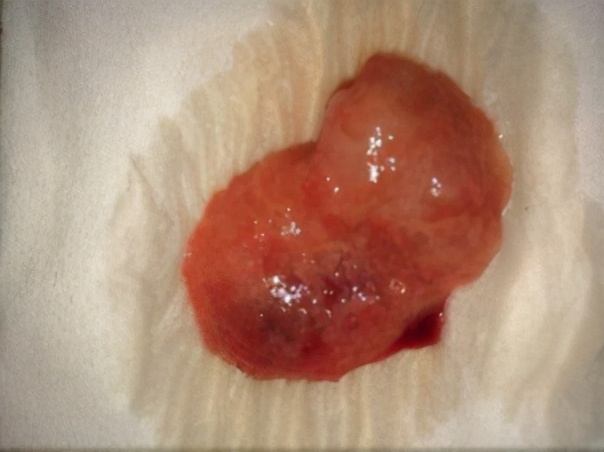

我先给小李安排口服米非司酮片25mg/次,一日2次,口服三天,服药前后禁食2小时,促使子宫蜕膜变性坏死、宫颈软化。在第四天的时候,让小李早上起来之后服用药物米索前列醇片600ug/次,这个药物可以让她的子宫兴奋、收缩,促使胚胎排出。服药后我安排了护士观察小李腹痛及阴道出血情况。1小时后小李出现轻微腹痛和不适,阴道有少量出血。在用药4小时后小李排出一完整孕囊(见图),出血量不多。最后我给予预防感染,促进子宫收缩等对症治疗。